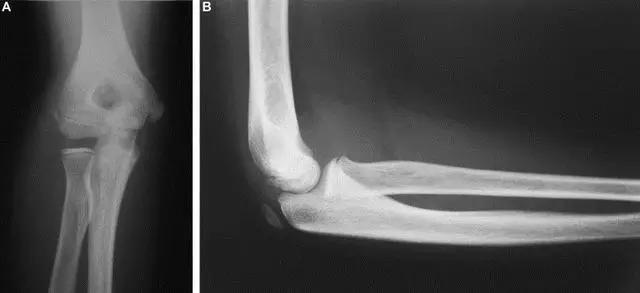

5. Kocher-Lorenz 骨折

单纯肱骨小头骨折。

6. Hahn-steinthal 骨折

全肱骨小头骨折,为一种少见的关节内骨折,多见于成年人。常由于跌倒时手过度伸直或在屈肘时因桡骨小头撞击肱骨小头,并同时有外翻力存在时发病,亦可伴有滑车骨折与内侧副韧带的撕裂。X 线表现为全肱骨头骨折,向上移位。

Hahn-steinthal 骨折 X 片(来源:Hahn-Steinthal fracture: a case report.BioMed central Cases Journal20081:239)

Hahn-steinthal 骨折 CT 片(来源:Hahn-Steinthal fracture: a case report.BioMed central Cases Journal20081:239)